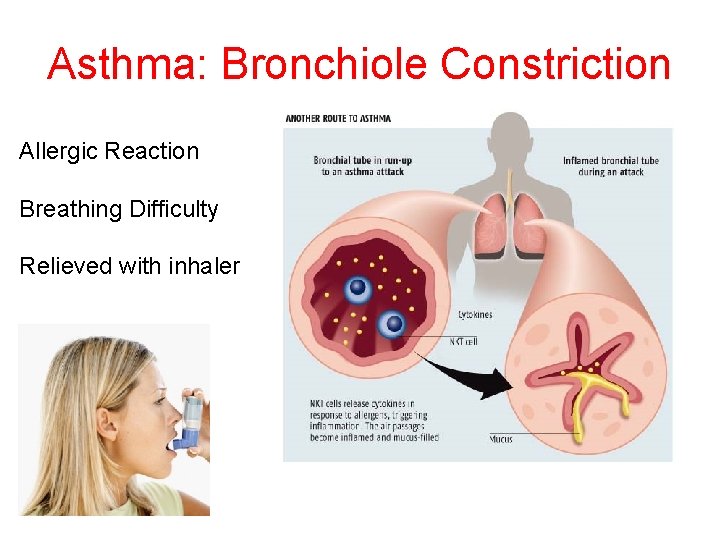

Asthma: Bronchiole Constriction Allergic Reaction Breathing Difficulty Relieved with inhaler